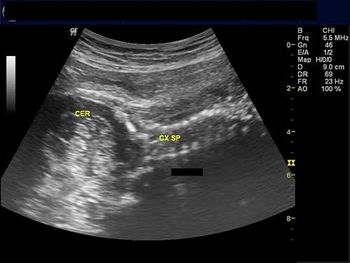

These images from a routine ultrasound examination of a 20-week fetus reveal a rare abnormality of the fetal spine.